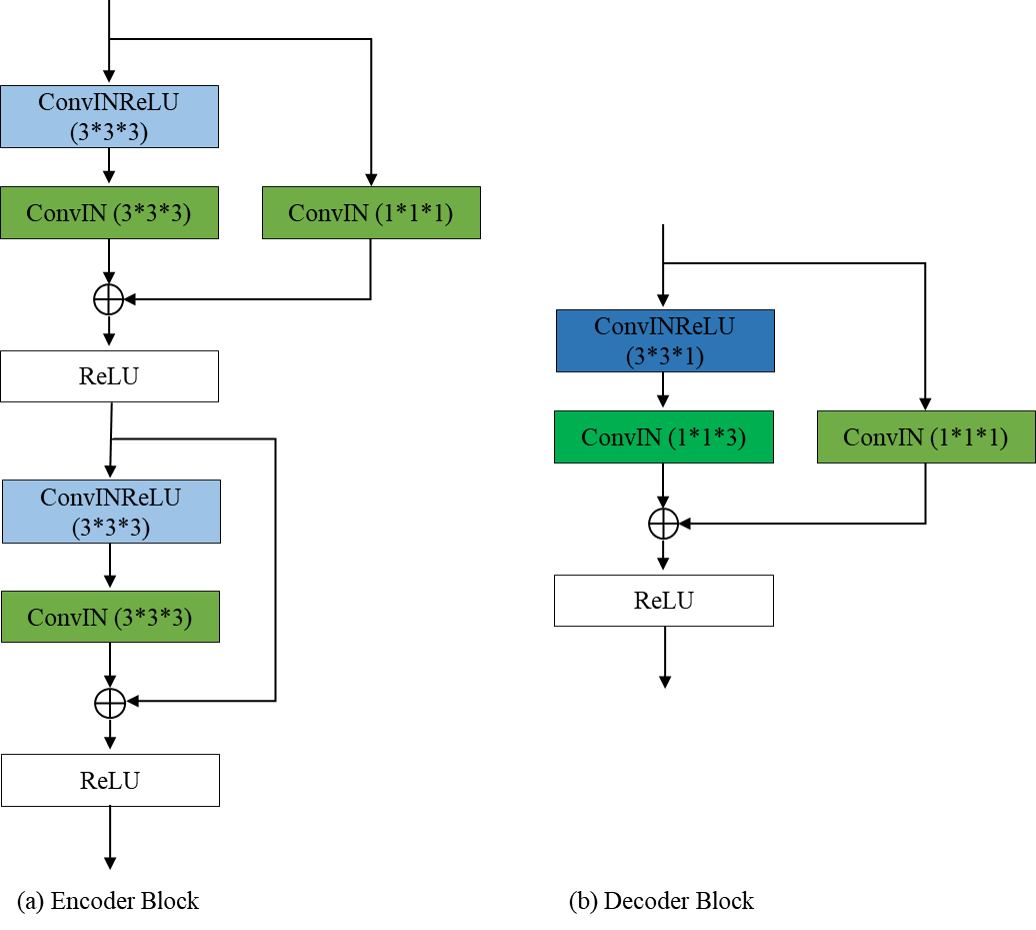

Encoder/Decoder

如图所示,编码器模块由两个残差卷积块组成,解码器模块由一个残差卷积块组成。在解码器模块中,我们将一个核大小为3×3×3的标准3D卷积分离为3×3×1片内卷积和1×1×3片间卷积。残差卷积块的实现如下:convent -instnorm-ReLU- convent -instnorm-ReLU(残差的加入发生在最后一个ReLU激活之前)。

本文基于UNet,对Encoder、Decoder、Context block进行如下优化:

- 对比Basic Convolution、Bottleck Convolution、Depthwise Separable Convolution、Anisotropic Convolution,Encoder最优选择为Basic Convolution,Decoder最优选择为Anisotropic Convolution。相对于Basic Convolution,其他卷积方式具有更低的运算复杂度,但是分割指标存在一定程度的下降。Decoder采用更低复杂度的Convolution block,对于分割指标影响较小。

- 采用非对称的UNet结构,Encoder采用4层卷积block(包含2个residual block),Decoder采用2层卷积block(包含1个residual block)

- 网络结构:Encoder采用2个basic residual block,Decoder采用1个anisotropic residual block,Context采用AnisotropicAvgPooling